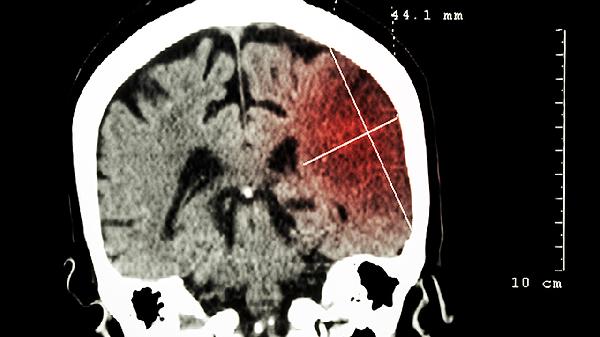

进展性加重的头痛伴喷射状呕吐提示颅内压增高,常见于硬膜外血肿。单侧瞳孔扩大对光反射迟钝可能预示脑疝形成。肢体无力或抽搐发作多与对冲伤引起的脑实质损伤相关。婴幼儿表现为异常哭闹、拒食或前囟膨隆时,家长须立即送医。老年人服用抗凝药物者即使轻微外伤也可能导致慢性硬膜下血肿,症状往往在1-3周后显现。

建议伤后保持安静休息,避免剧烈活动。24小时内每2小时评估意识状态,记录症状变化。禁止服用阿司匹林等影响凝血药物。饮食选择易消化食物,控制饮水量。出现新发症状或原有症状加重时,应立即前往急诊科进行头颅CT检查。恢复期出现注意力不集中、睡眠障碍等脑震荡后综合征表现时,需神经科随访。